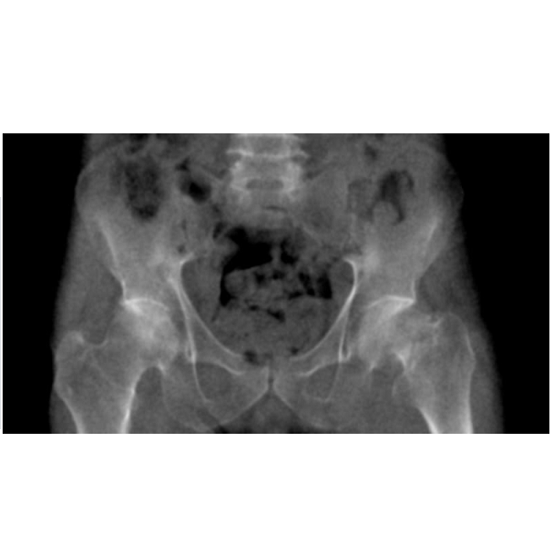

Pelvic phantom with femoral neck fracture for CT

NLP1200 Pelvic phantom with femoral neck fracture for CT, X-ray and radiation therapy

用於 CT、X 射線和放射治療的股骨頸骨折骨盆模型。

骨盆模型提供了對左側股骨頸骨折輕微脫位的本地男性骨盆的真實模擬。體模包括整個骨盆和第五腰椎。

尺寸:27x17x16cm